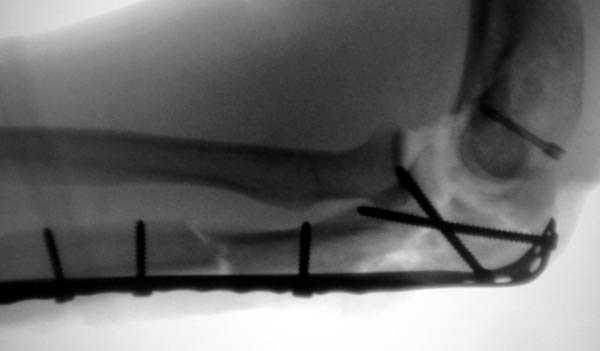

3 вариант

перелом с capitellum humerus и проксимальной трети улна